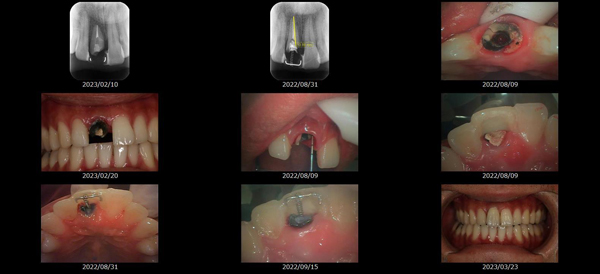

救歯MTM

虫歯が大きくて残せない歯、転倒などの事故により歯が根の深いとこで折れてしまったなどで、抜かざるを得ない歯を、骨の中に埋まっている健全な根を、骨の上に矯正的に引き上げることで、その歯を抜かず温存、救歯できる可能性のある治療方法です。

この特別な診療である救歯MTMは、以下のような特徴があります。

①健全な歯を、歯肉から見える位置にまで引き上げることで

根の治療の成功率を上げることが出来る。唾液には沢山の細菌がいます。唾液が入らない環境での根の治療を(神経の治療)を行うことで神経の治療、根の治療の成功率は格段と上がります。

②骨の上にある歯と土台で支える被せもの製作できる。

被せものを土台だけに頼ることなく、引き上げた健全な歯でも支えることで、歯への被せ物がしっかりと装着できるようになる。

③抜かずに歯を活かすことで、隣の歯を削るブリッジやインプラントにしないで済むことがある。

歯を矯正的に引き上げることで、その歯を救歯できるだけでなく、隣の歯を削るなどの侵襲を回避できる場合がある。

救歯治療と審美性の両立

当院では様々な治療の基礎に審美と機能の両立というテーマがあります。

リスク

- > 歯を矯正的に引き上げることで、骨の中の根の長さは短くなりますが、その短さでも安定するという診断をした場合のみ施術になります。 残せる歯、根の長さが短い場合は、この救歯MTMの治療対象とならない場合がございます。

- > 治療期間が数か月~1年に及ぶ場合がある。

- > 費用が自費診療 44,000円 ~ 66,000円

- > 救歯MTMは救歯BTAセラミックと併用治療が必要な場合があります。

症例